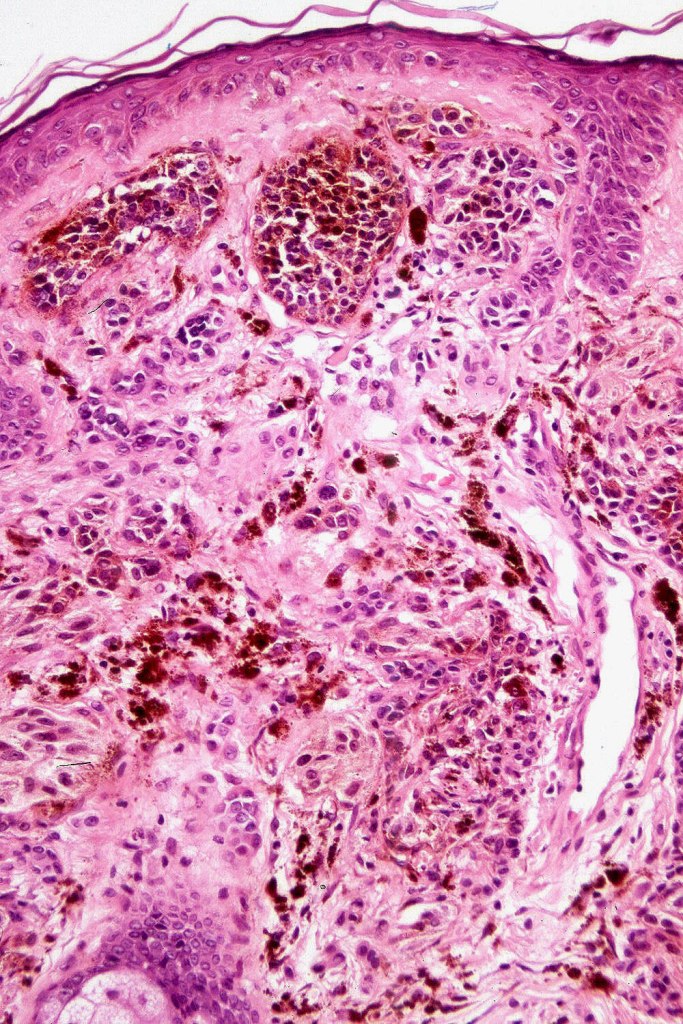

Combined common & deep penetrating nevus